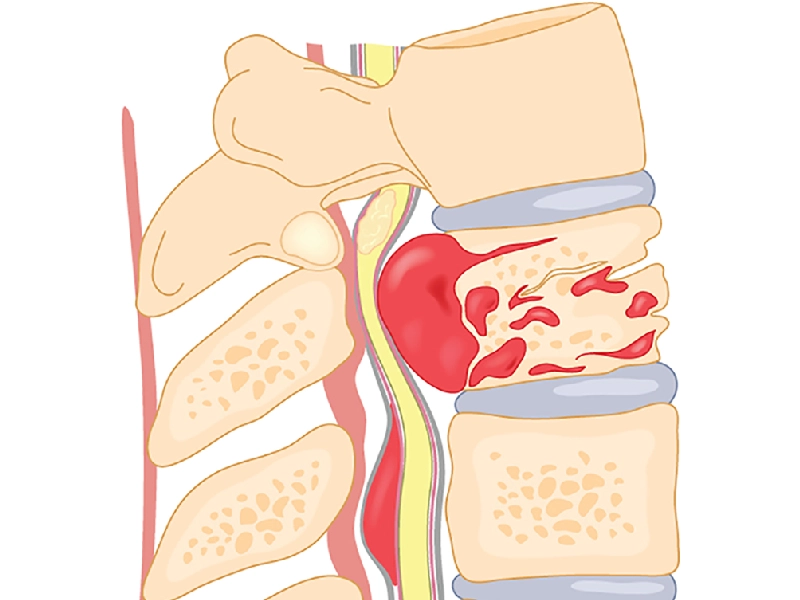

دیسک کمر یکی از شایعترین دلایل کمردرد در میان بزرگسالان است. بر اساس آمارها، بیش از ۸۰ درصد افراد در طول زندگی خود حداقل یکبار کمردرد را تجربه میکنند و در بسیاری از این موارد، آسیب به دیسک بین مهرهای عامل اصلی است. آشنایی با ساختار دیسک، انواع آسیبها، علائم...

دیسک کمر یکی از شایع ترین مشکلات ستون فقرات است که زندگی روزمره فرد را تحت تاثیر قرار میدهد. این عارضه به دلیل بیرون زدگی یا آسیب دیدگی دیسکهای بین مهرهای بهوجود میآید و اغلب با درد، بیحسی یا گزگز در ناحیه کمر و پاها همراه است. با پیشرفت علم...